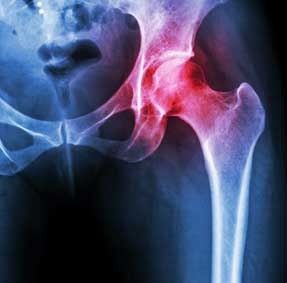

Mako is a technique used by surgeons for partial knee resurfacing, total knee replacement and total hip replacement. It is an innovative treatment option for adults living with early to mid-stage joint degeneration of the hip or knee.

It all begins with a CT scan of your knee or hip joint, which is used to generate a 3D virtual model of your unique anatomy. This virtual model is loaded into the Mako System software and used by your surgeon to create a personalized pre-operative plan.

After surgery, your surgeon, nurses and physical therapists will set goals with you to get you back on the move. They will closely monitor your condition and progress. Your surgeon may review a post-operative x-ray of your new joint with you.